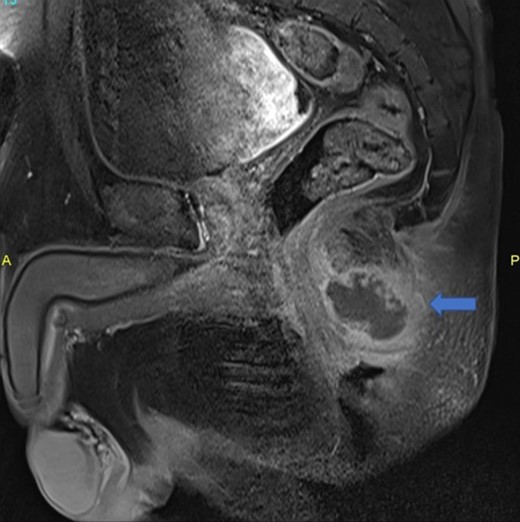

The patient was febrile (38.5°C) and restless. Proctologic examination revealed a painful swelling on the posterior midline, around which the leech bites could be seen (Fig. 1). He was immediately hospitalized, and a rapid pelvic MR, blood tests and anesthesia with epidural catheter were organized. Blood tests revealed a WBC count of 22 000/ml and sedimentation rate of 80 mm/h. A posterior perianal midline fluid collection measuring up to 4 × 3 cm was detected on MRI. The collection had thick and strongly enhancing walls with central diffusion restriction on diffusion weighted series, consistent with abscess. Inflammatory findings around the abscess were affecting both sides of the natal cleft (Fig. 2).

Posterior midline perianal fluid collection with thick enhancing walls was demonstrated on sagittal postcontrast fat saturated T1 weighted image (arrow) consistent with abscess.